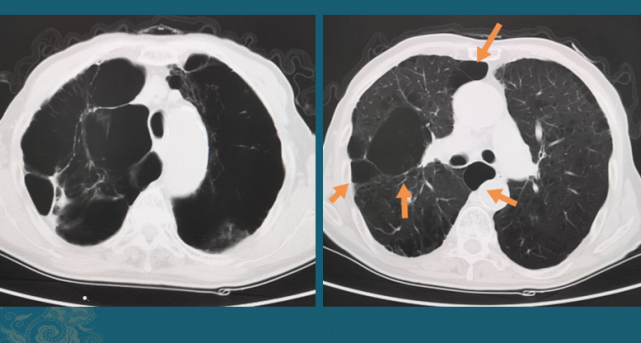

多出来的肺裂,你认识几个?

多出来的肺裂你认识几个